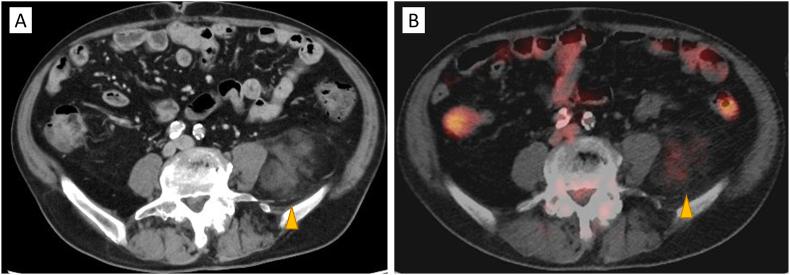

Extra-adrenal myelolipoma in the pelvis: A great mimicker of liposarcoma.

Radiol Case Rep. 2025 Jul 23;20(10):5099-5102. doi: 10.1016/j.radcr.2025.06.075. eCollection 2025 Oct.